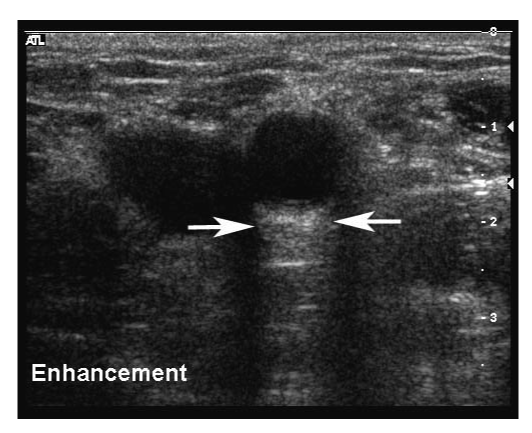

Acoustic enhancement seen distal to a low attenuating structure.

_page_16.png?sfvrsn=4386c723_2)